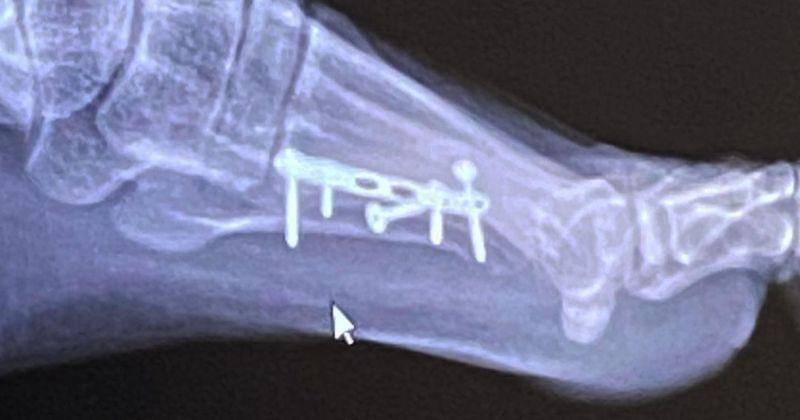

3. Beberapa kali operasi tulang di bagian kaki

Michelle Hendra juga menceritakan bahwa dirinya sempat mengalami patah tulang kaki hingga harus dioperasi. Kala itu, dokter menganjurkan Michimomo untuk memasang pen penyanggah tulang di kakinya.

Namun, sayangnya ketika ia pulang dari Bali. Pen penyanggah itu terlepas karena tersandung saat berjalan.

"Pernah juga, cuma keluar dari taksi tapi ternyata emang tulang saya lemah, ya. Bengkak kakinya, terus udah dipasang pen. Terus tiba-tiba lagi pergi ke Bali, pas pulang ternyata bautnya copot, jadi harus operasi lagi untuk copotin bautnya itu," jelas Michelle.